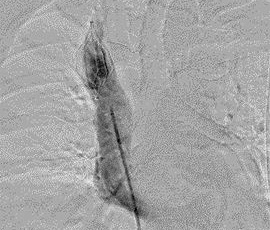

CR画像(上大静脈フィルター留置)